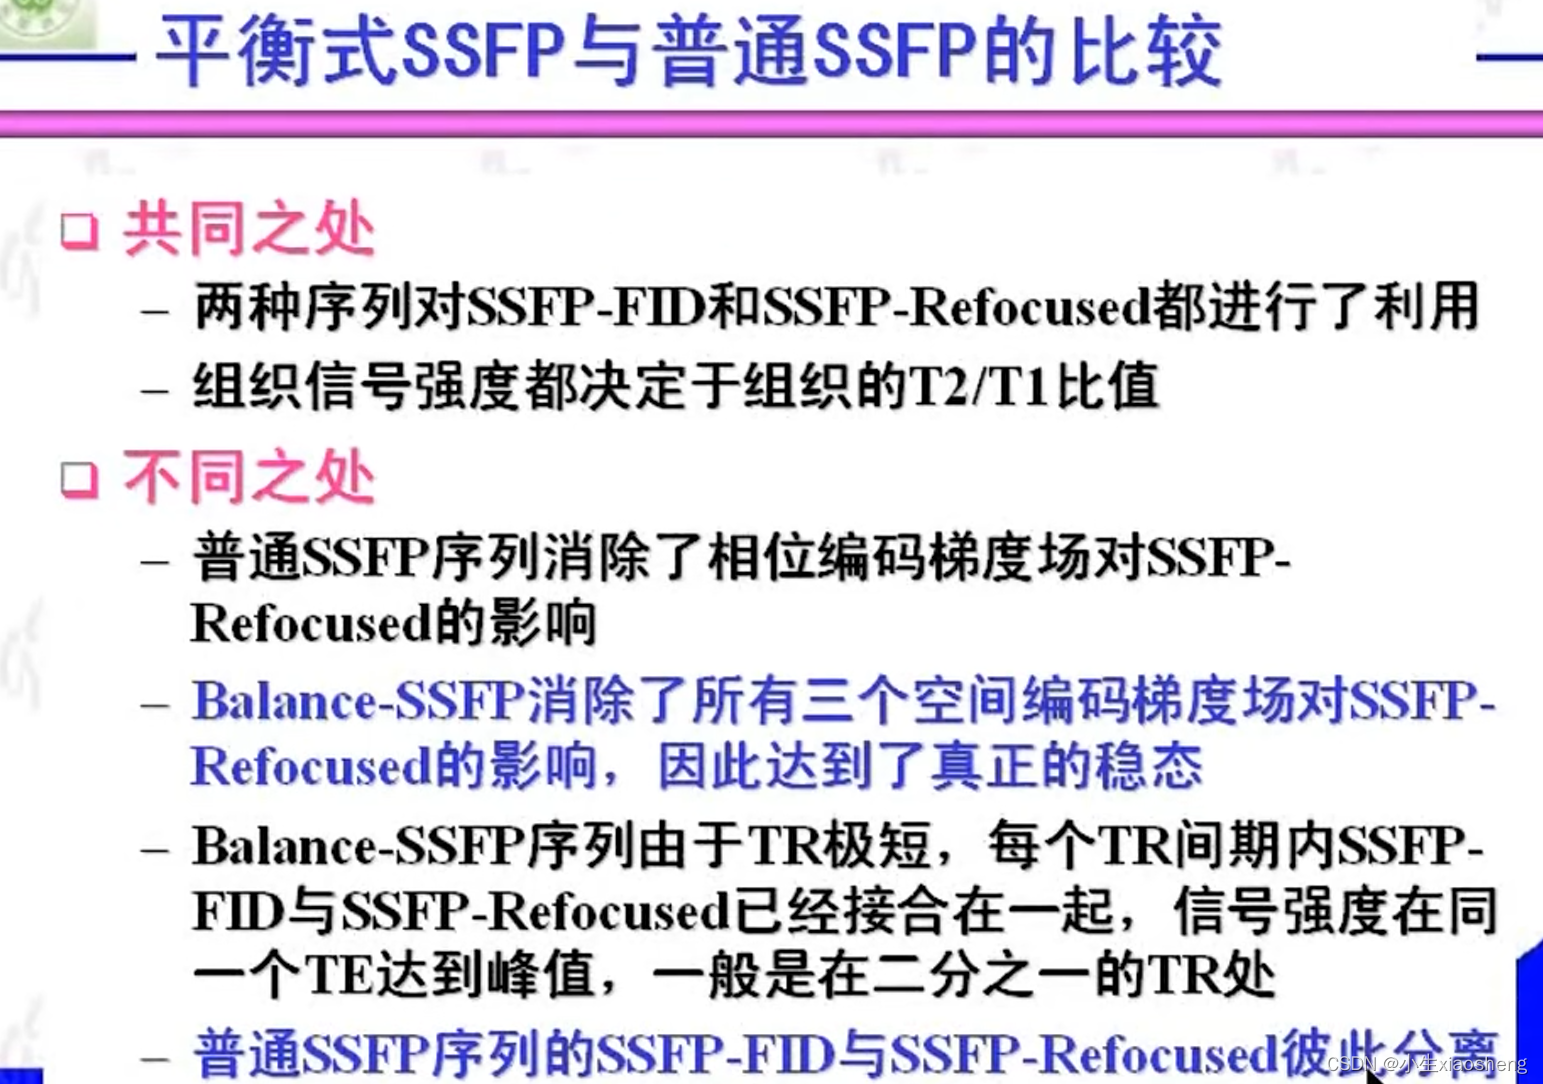

3.平衡SSFP序列

TR和TE要小一点能得到更好的效果图片。

2.普通SSFP序列

梯度场抵消:SSFP序列的一个显著特点是,在Gx、Gy、Gz三个方向梯度场的正反切换完全抵消。这种抵消作用使得流动的信号得到补偿,从而在图像中减少或消除流动伪影。

在实际应用中,SSFP序列通常用于心脏成像、血管成像和腹部成像等领域。由于其较快的扫描速度和较高的信噪比,SSFP序列可以大大提高成像效率和质量。然而,SSFP序列也存在一些局限性,例如对磁场不均匀性较为敏感,可能产生伪影等。因此,在实际应用中需要根据具体情况选择合适的成像参数和扫描方法。

此外,SSFP序列还与其他技术相结合,形成了多种改进型的SSFP序列,如平衡SSFP(Balanced SSFP)序列等。